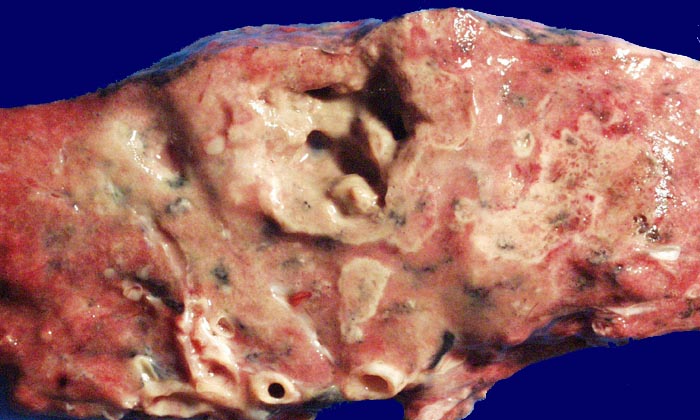

PathoPic ID 49 - Pilzpneumonie (invasive Aspergillose) mit Kavernenbildung

Pilzpneumonie (invasive Aspergillose) mit Kavernenbildung

Weisse Herde im fixierten Lungenparenchym entsprechen mykotischen pneumonischen Herden. Ein grösserer Herd ist zentral nekrotisch eingeschmolzen.

Mykotische Meningoenzephalitis und Pilzpneumonie bei metastasierendem Magenkarzinom